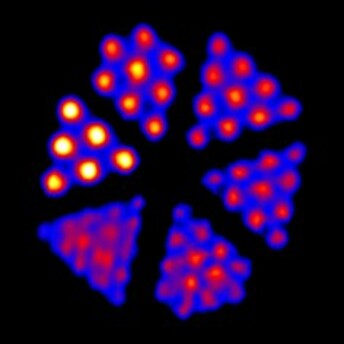

Derenzo模體的示例圖像,包括在Bruker BioSpin MRI系統上成像的1.0 mm至1.5 mm模式Derenzo(上)和在Inveon PET / CT系統上成像的F-18成像的0.7 mm至1.5 mm模體(下)

只需確定給定的同位素和計數值即可分辨的最小孔組,即可啟用掃描儀的分辨率測試。我們的Derenzo模體具有六種不同的孔尺寸,它們圍繞模體以三角形排列。